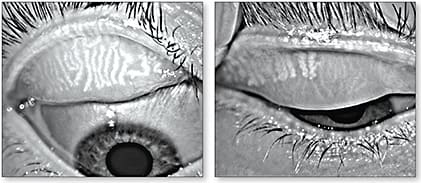

Of interest, there is a higher frequency of MGD in contact lens wearers.15 A 2016 study evaluated the effect of long-term contact lens wear on the morphology of meibomian glands using meiboscore and digital analysis.16 This study determined that long-term lens wear of more than three years can cause meibomian gland loss. The authors advised that digital analysis is helpful in the morphologic evaluation of meibomian glands. When evaluating MGD, it is helpful to determine whether eyelid telangiectasia is present, the number of glands present, whether there is any evidence of meibomian gland orifice obstruction, and whether there is decreased quality of meibomian gland secretions. Meibomian gland dropout can be visualized using transillumination or infrared photo imaging (Figure 1).